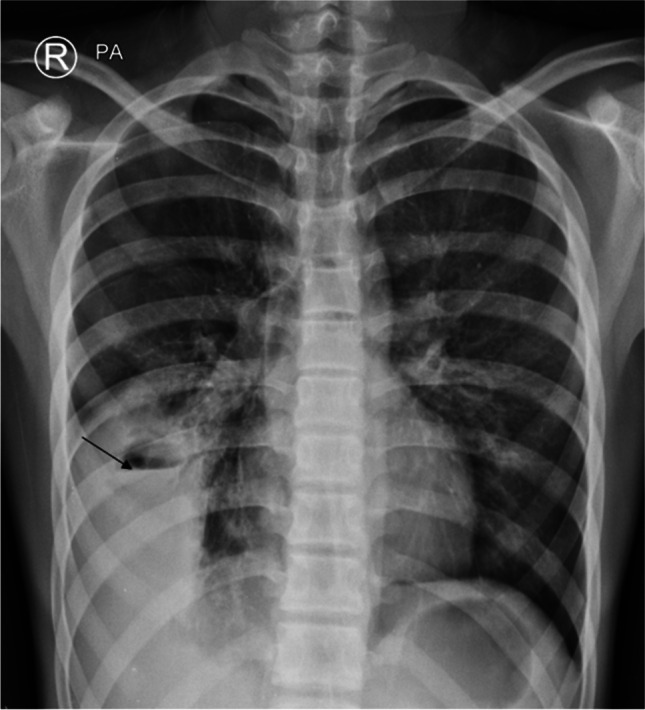

The radiological features of pneumonia caused by C. psittaci are large areas of consolidation or ground-glass opacities, typically bilateral and involving multiple lobes (Fig. 5). Mild to moderate pleural effusion is a common accompanying finding, while mild pericardial effusion is less commonly seen [49]. Neither the radiological features nor the clinical course is specific for diagnosis. Therefore, the potential of a history of contact with birds should be considered in any case of unexplained atypical pneumonia.

Fig. 5.

Coronal non-contrast-enhanced lung window computed tomography image in a 3-year-old boy affected by psittacosis who presented with severe dyspnea. The image shows multiple bilateral lung consolidations (arrows) (figure from “A pediatric case of Chlamydia psittaci caused severe Acute Respiratory Distress Syndrome (ARDS) in Italy” by Marchese et al.; licensed under CC BY; original annotated)